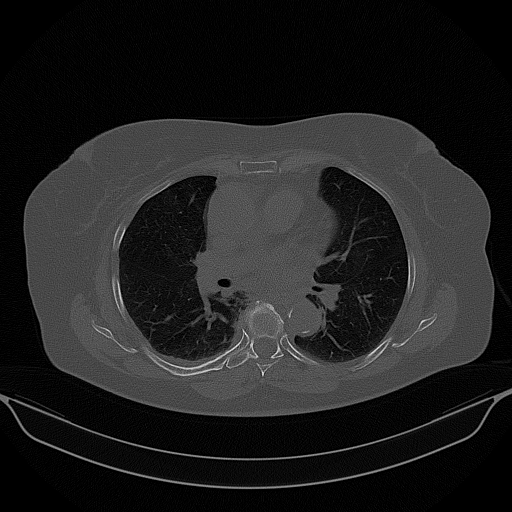

Targeted Slice 70 - Lung Window Analysis (Generated vs Real Venous)

0.676

Lung SSIM

119.5

Lung RMSE

52.1

Lung MAE

Average Lung Window Metrics Across All Slices (58 slices) - Generated vs Real Venous

0.690

Lung SSIM (Avg)

110.0

Lung RMSE (Avg)

49.3

Lung MAE (Avg)

Generated VENOUS CT scan (A→B translation)

No window - Raw intensity values

Lung window (WL -600, WW 1500 β†’ Low βˆ’1350, High +150)